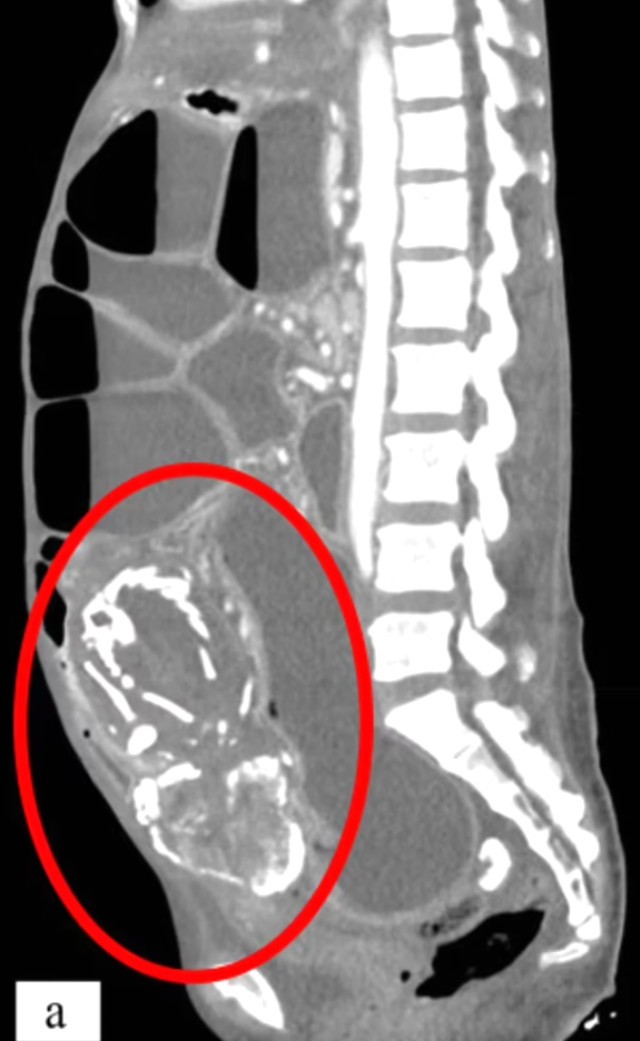

Belə ki, 9 il əvvəl qadının bağırsaqlarında uşaqlıq yerinə döl əmələ gəlib və bu döl zamanla daşa çevrilərək bağırsaqlarını bağladığı üçün onun ölümünə səbəb olub.

Hadisə ilə bağlı açıqlama verən Dr. Waseem Sous, 50 yaşlı qadının daha əvvəl şikayətləri olduğunu, lakin əməliyyat olunacağından qorxaraq müalicədən imtina etdiyini bildirib.